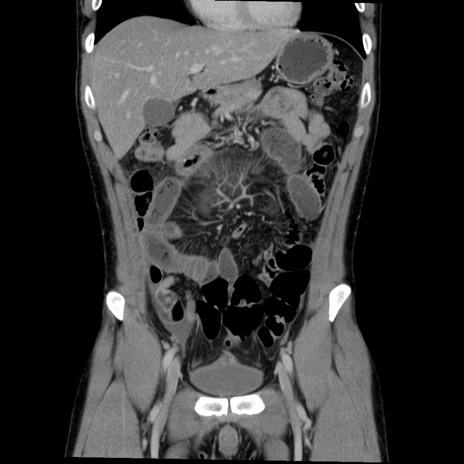

症例36(冠状断像)

【症例】20歳代 男性

【主訴】心窩部痛

【現病歴】今朝より上腹部痛あり。一旦軽快していたが再度出現したため救急要請。昨日夕に白身の魚を含む刺身を食べた。

【身体所見】BP 136/89mmHg、HR 74/min、BT 37.0℃、腹部:膨満、軟、心窩部に圧痛あり。反跳痛なし、筋性防御なし、腸雑音やや亢進あり。

【データ】WBC 17700、CRP 0.48